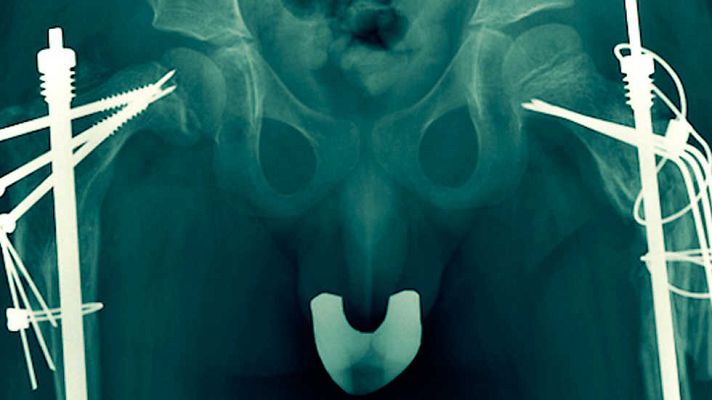

Documental sobre el trastorno genético llamado Osteogénesis Imperfecta,también conocido como la enfermedad de los" huesos de cristal".Son niños que sufren reiteradas fracturas al hacer el menor movimiento,incluso tan solo al respirar.